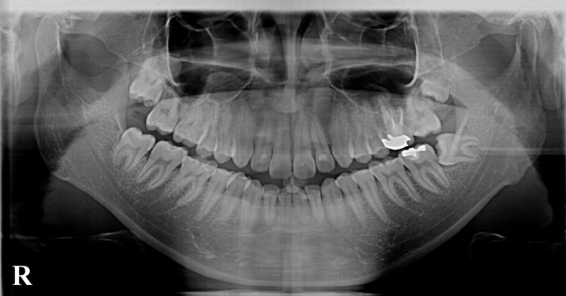

被曝量の少ないデジタルレントゲンをはじめ、針の細い電動注射器など、様々な機器を活用して、患者様の身体に負担をかけず痛くない治療を目指しております。

初めて来院頂きましたら、まずはレントゲン撮影を行うことがほとんどです。

当院では通常の2分の1以下という低線量での撮影が可能なデジタルレントゲンを使用しております。